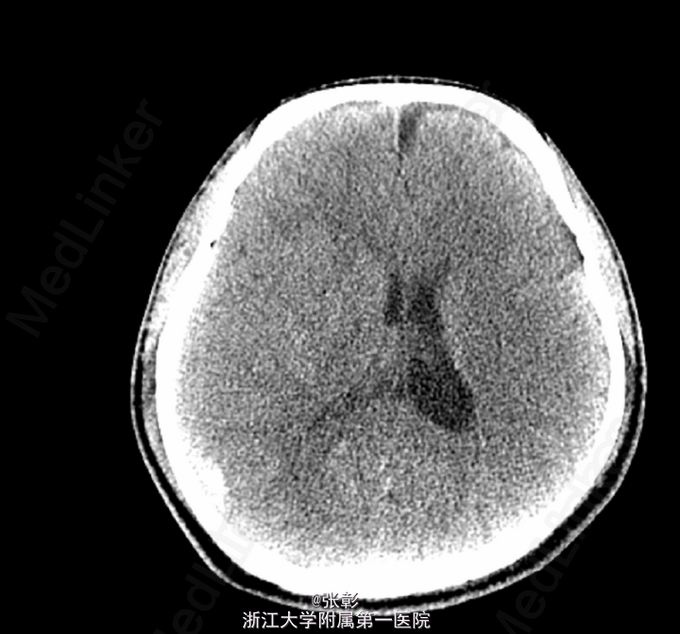

初步诊断:亚急性硬膜下血肿. 入院后行各项检查,(2015-06-24 11:40)血常规(五分类)(全血):白细胞计数9.2×10^9/L、血红蛋白139g/L、血小板计数245×10^9/L、(2015-06-24 10:57)电解质全套(血清):白蛋白45.9g/L、钾3.87mmol/L、钠138.0mmol/L、肌酐79μmol/L、甘油三酯1.89mmol/L↑、C-反应蛋白7.1mg/L、(2015-06-24 14:25)肿瘤标记物全套(男)(血清):癌胚抗原1.2ng/mL、甲胎蛋白1.9ng/mL、癌抗原1996.0U/mL。(2015-06-23 19:42)行CT(头部)检查提示:脑动脉CTA检查未见异常CT征象。右侧额颞顶部硬膜下血肿。进一步行脑血管造影:脑血管造影未见明显异常。给予对症支持治疗。